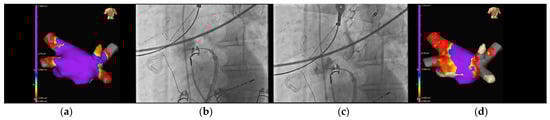

- In several clinical scenarios, the use of this new CB feature has helped the operator to reach an easier PVI, such as in cases with common PV trunks, accessory PVs, and funnel-shaped PV ostia.

4.2. Case-Based Approach